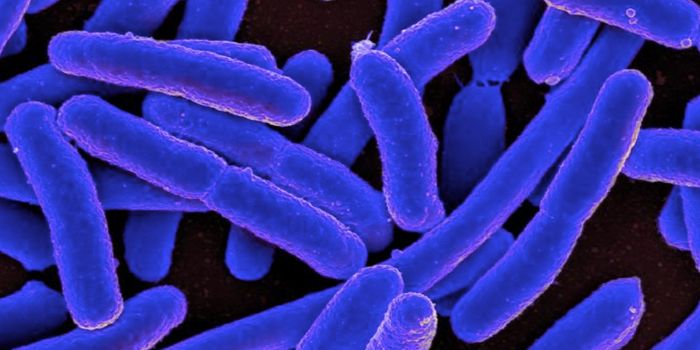

SEP 09, 2025MicrobiologyThe World Health Organization has estimated that in 2022, at least 149 million children under 5 were too short for their ...

JUN 24, 2025MicrobiologyMany important antibiotics are becoming less effective against bacterial infections, as bacteria continue to evolve, gai ...